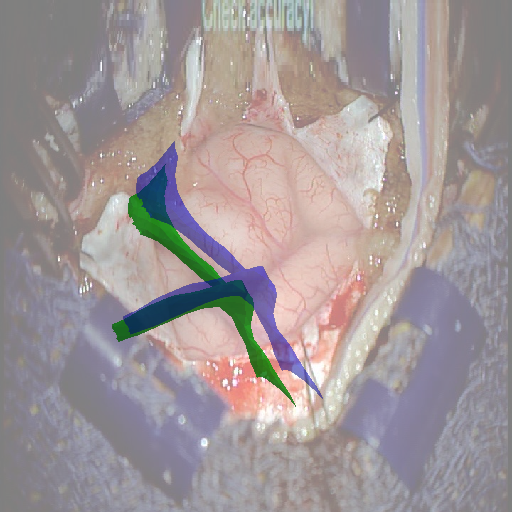

We tested our method retrospectively on 6 clinical datasets from 6 patients (cases) (see Fig. 5). These consisted of preoperative T1 contrast MRI scans and intraoperative images of the brain surface after dura opening. Cortical vessels around the tumors were segmented and triangulated to generate 3D meshes using 3D Slicer. We generated 100 poses for each 3D mesh (i.e.: each case) and used a total of 15 unique textures from human brain surfaces (different from our 6 clinical datasets) for synthesis using . In order to account for potential intraoperative brain deformations [4] we augment the textured projection with elastic deformation [21] resulting in approximately 1500 images per case. The surgical images of the brain (left image of the stereoscopic camera) were acquired with a Carl Zeiss surgical microscope. The ground-truth poses were obtained by manually aligning the 3D meshes on their corresponding images.

Test and Comparison on Clinical Images

We compared our method (Ours) with segmentation-based methods (ProbSEG) and (BinSEG) [7]. These methods use learning-based models to extract binary images and probability maps of cortical vessels to drive the registration. We report in Tab. 1 the distances between the ground truth and estimated poses. Our method outperformed ProbSEG and BinSEG with an average ADD error of mm compared to mm and mm, respectively. Our errors remain below clinically measured neuronavigation errors reported in [4], in which a mm average initial registration error was measured in 15 craniotomy cases using intraoperative ultrasound. Our method outperformed ProbSEG in 5 cases out of 6 and BinSEG in all cases and remained within the clinically measured errors without the need to segment cortical vessels or select landmarks from the intraoperative image. Our method also showed fast intraoperative computation times. It required an average of only milliseconds to predict the pose (tested on research code on a laptop with NVidia GeForce GTX 1070 8GB without any specific optimization), suggesting a potential use for real-time temporal tracking.

Fig. 5 shows our results as Augmented Reality views with bounding boxes and overlaid meshes. Our method produced visually consistent alignments for all 6 clinical cases without the need for initial registration. Because our current method does not account for brain-shift deformation, our method produced some misalignment errors. However, in all cases, our predictions are similar to the ground truth.